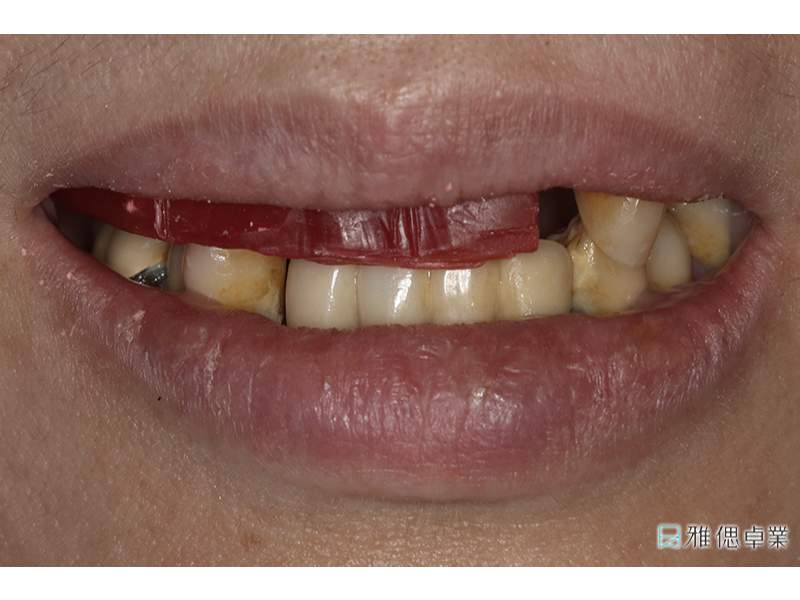

術前環口X光片,上顎只剩下2顆牙齒,下顎也有牙周、排列、咬合等問題

術前